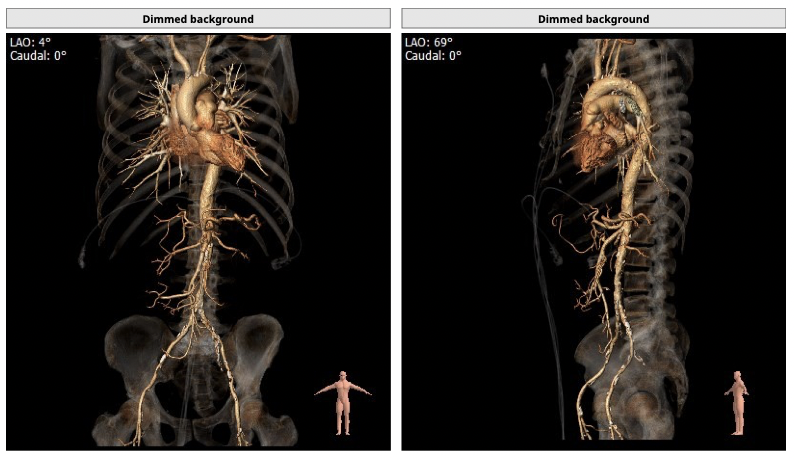

CT检查

①患者因规律透析导致钙磷代谢紊乱,外周血管斑块钙化严重,最狭窄处仅2.8mm,通路建立难度极大(左右颈动脉均不符合入路条件);

确保冠脉安全,拟采取PCI+TAVR一站式手术策略,因患者右侧股动脉钙化严重、入路狭窄,拟采取无鞘法从右股动脉穿刺入路,选用20mm球囊预扩、L23号VenusA-Valve瓣膜、采用VenusA-Plus输送系统确保瓣膜的精确释放,瓣膜释放后结合造影和超声情况,决定是否后扩。